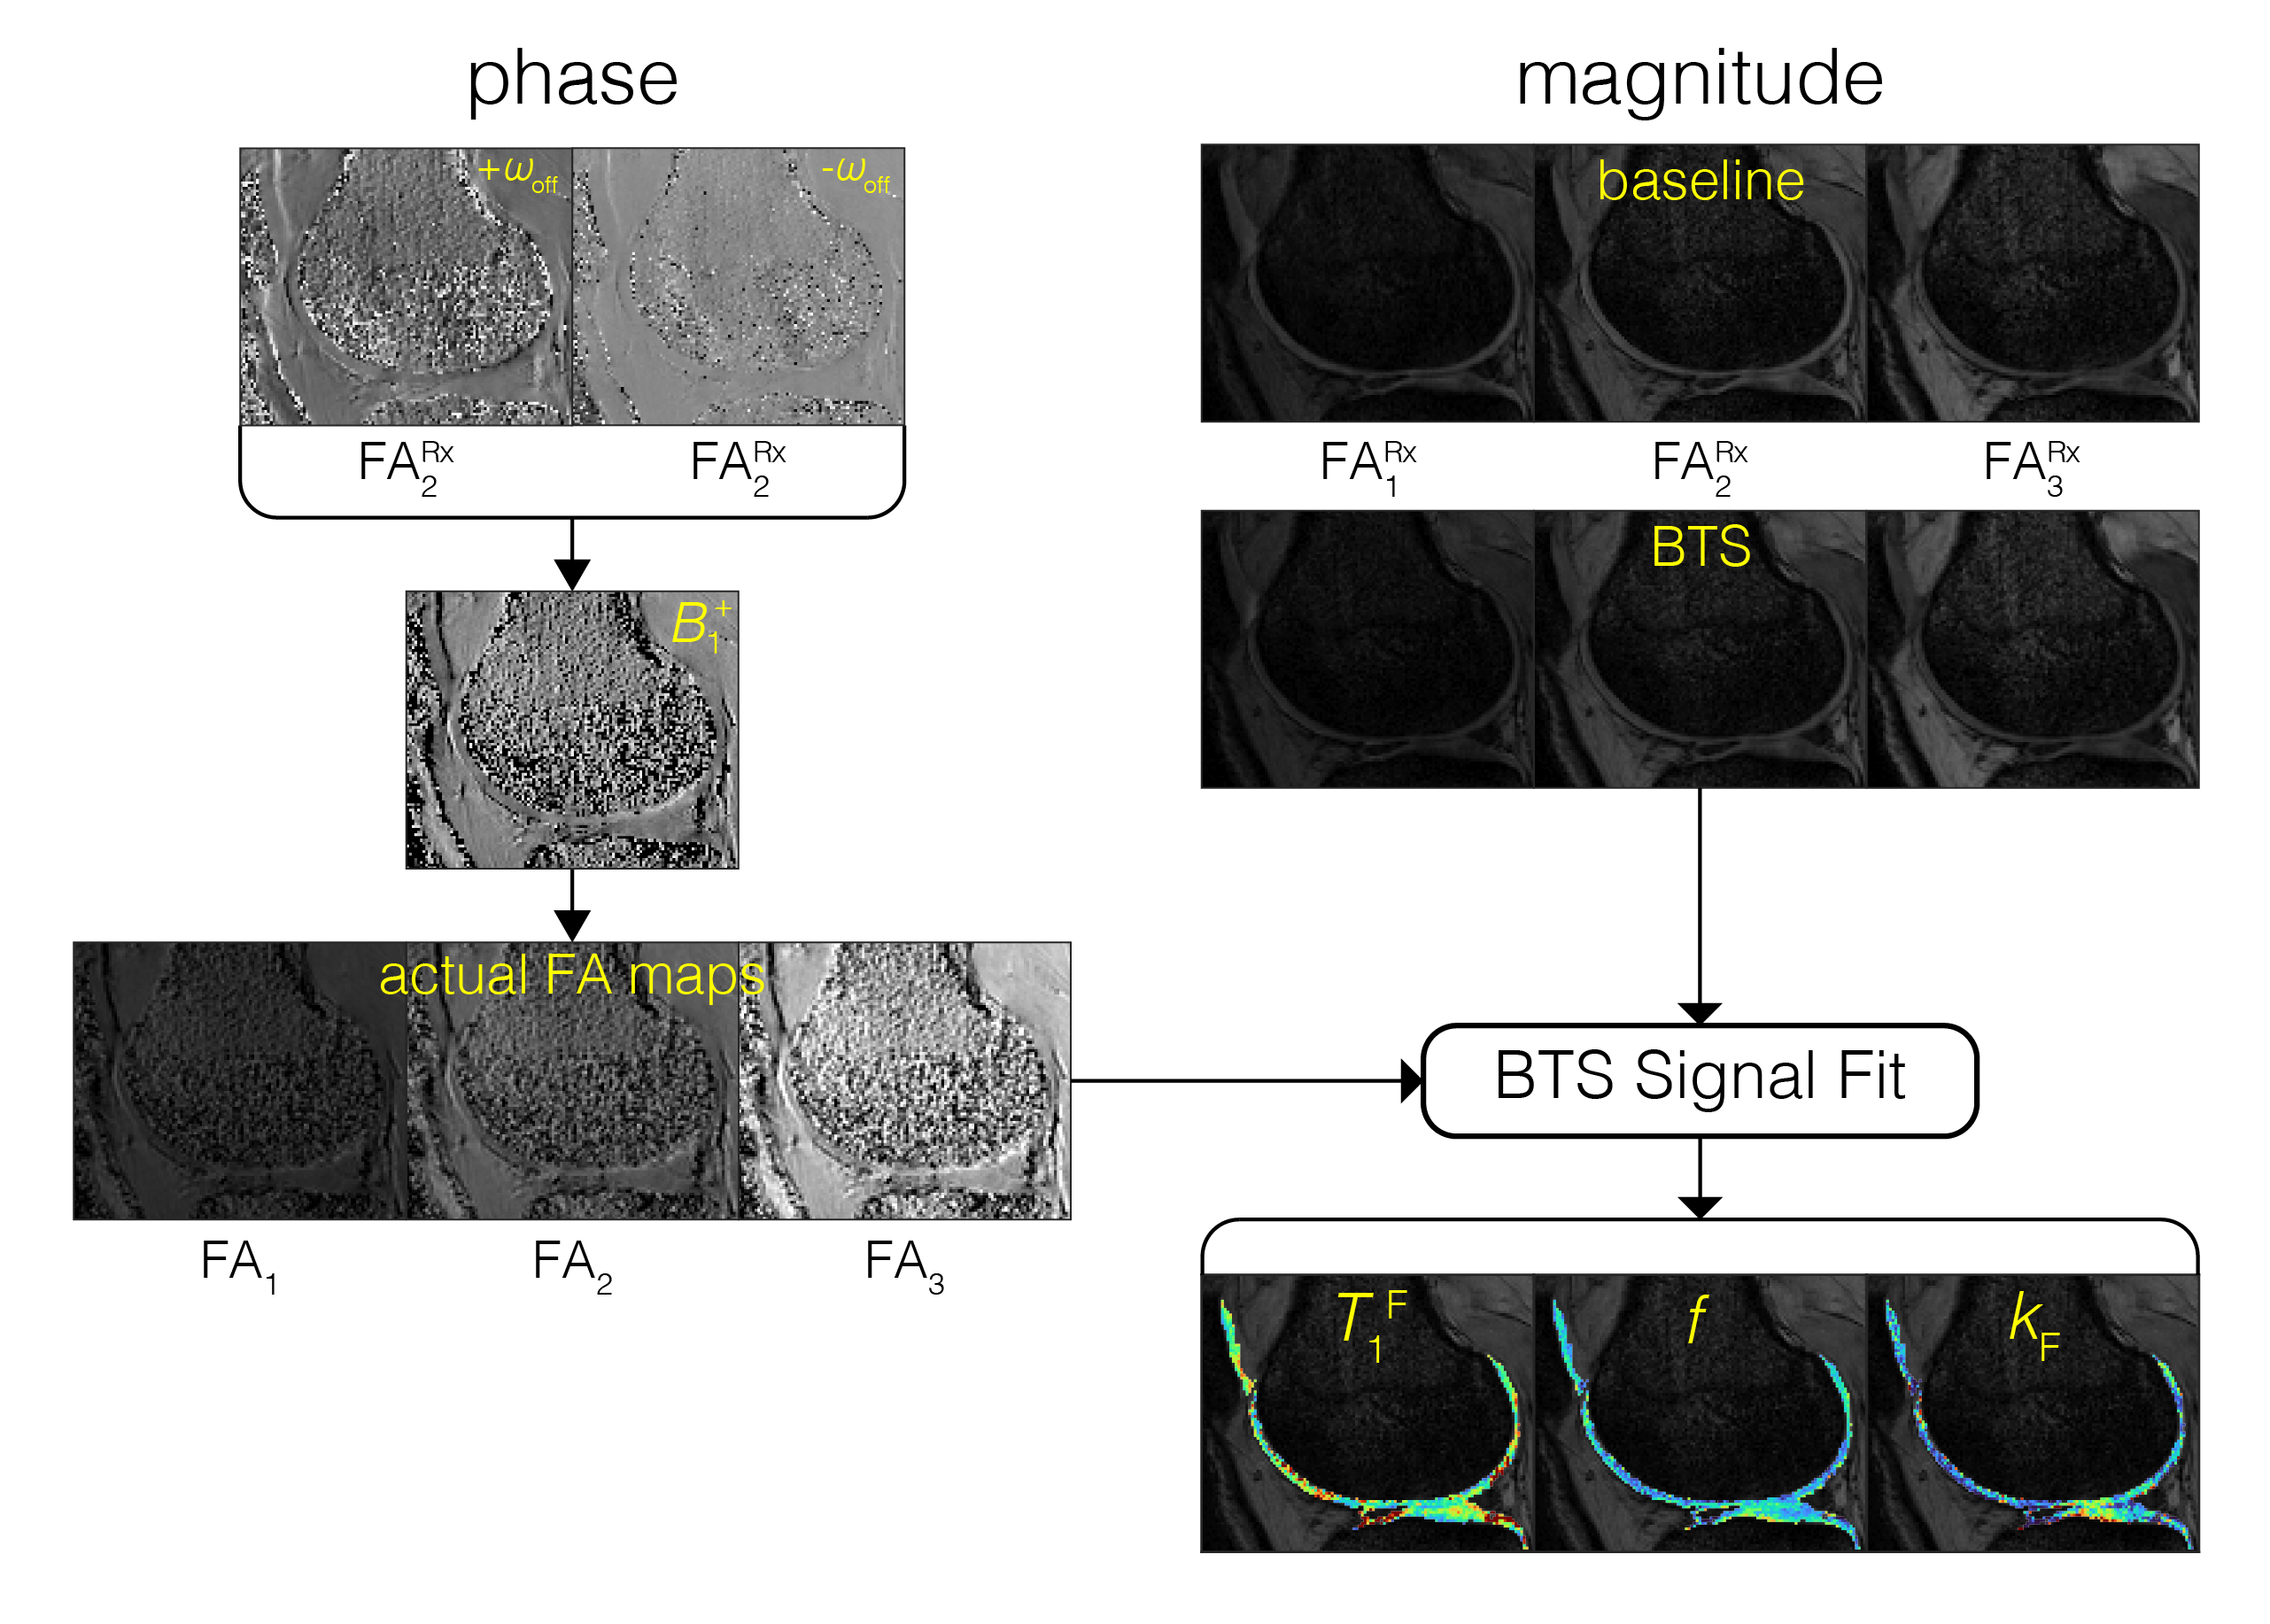

The BTS method is based on an RF-spoiled gradient-echo scheme. Off-resonance irradiation, whose frequency is significantly larger than its peak amplitude and Larmor frequency (ωoffω1max, ωo), is introduced between excitation and acquisition (FIG1A). Adding off-resonance RF induces two independent effects: 1) MT through direct saturation of macromolecules and 2) B1+ dependent Bloch-Siegert phase shift6 of free water protons. Utilizing the binary spin-bath system, the Bloch-McConnell equations can be solved in the steady-state to obtain an analytical signal equation (FIG1C), whereby MT is encoded through signal magnitude and B1+ through signal phase. Using a variable flip-angle (vFA) scheme with (BTS) and without (baseline) off-resonance RF applied, these signal terms are used to generate a B1+ map, T1F (MT-corrected free water T1) map, and MT parameters f and kF maps.

BTS was validated through phantom and in-vivo knee experiments on a 3T scanner (Siemens Prisma). A 20-channel head coil was used for the phantom experiment, and a 4-channel flex coil was used for the in-vivo experiment. Phantom experiment: Phantoms consisted of four 20mL vials emersed in a 200μM MnCl2 water bath. Vials consisted of 2%, 4%, 8% agar (weight per volume) dissolved in DI water and boiled egg white. Common 3D parameters for both BTS and baseline acquisition: matrix size = 128x128x12 yielding 1.3x1.3x5mm resolution, TE/TR = 12/80ms, gradient spoiling moment = 600mT·ms/m, RF spoil increment = 169˚, and prescribed flip-angles (FAs) 5˚, 10˚, 20˚, 40˚, 60˚. For BTS acquisitions, an 8ms fermi MT saturation pulse with off-resonance frequency 4000Hz and effective flip-angle 786˚ was used, assuming a Gaussian absorption line shape3. In-vivo experiment: Common 3D parameters for both BTS and baseline acquisition: matrix size = 224x192x36 yielding 0.7x0.7x3mm resolution along the sagittal plane, TE/TR = 12/70ms, gradient spoiling moment = 320mT·ms/m, RF spoil increment = 169˚, and prescribed flip-angles 10˚, 20˚, 40˚. MT saturation pulse with effective flip-angle 629˚ was applied for BTS acquisitions assuming a Super-Lorentzian absorption line shape8. An in-vivo knee scan was performed on a healthy subject. Inter-scan motion was compensated using the co-registration method9. The phase term of the BTS equation was used to estimate B1+6 and subsequently used to calculate the actual flip-angle maps to compensate transmitting field inhomogeneity. These were then applied to the magnitude term of the BTS equation to extract T1F, f, and kF, assuming fixed MT properties for macromolecule bound proton T1R = 1s and T2R = 12μs (FIG 2).

FIG 2. BTS fitting involves obtaining measurements at multiple flip-angles (FAs). With an additional BTS acquisition used to remove any B0 inhomogeneity and chemical shift dependence on the Bloch-Siegert shift, a B1+ map is derived and utilized to generate FA maps. The spatially varying actual FAs, BTS magnitude images and separately acquired baseline images (without off-resonance pulse applied at multiple FAs) are used to fit the BTS signal equation pixel by pixel, generating T1F, f and kF maps. Superscript Rx denotes prescribed FA.